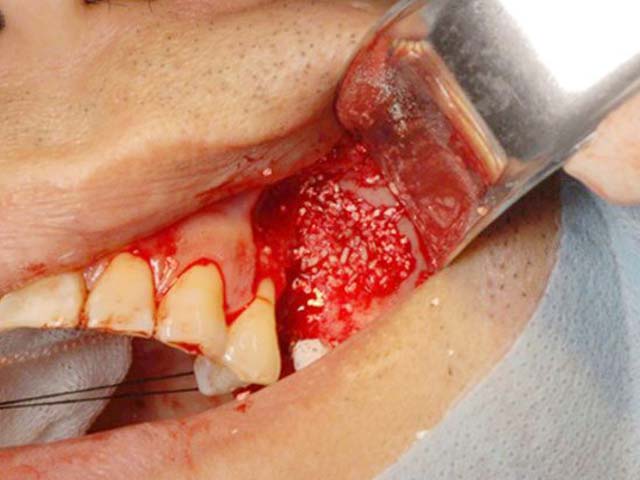

鼻竇增高術(側窗) 首頁 案例分享 人工植牙 鼻竇增高術(側窗) 鼻竇增高術(側窗) 製作多年的牙橋,牙根斷裂,發炎 鼻竇增高術 側面開窗 抬高鼻竇 鼻竇增高術 置入骨粉 覆蓋再生膜,保護骨粉 術後追蹤,傷口良好 裝戴正式假牙 完成 8年追蹤 左上牙根斷裂 植牙重建 九年追蹤